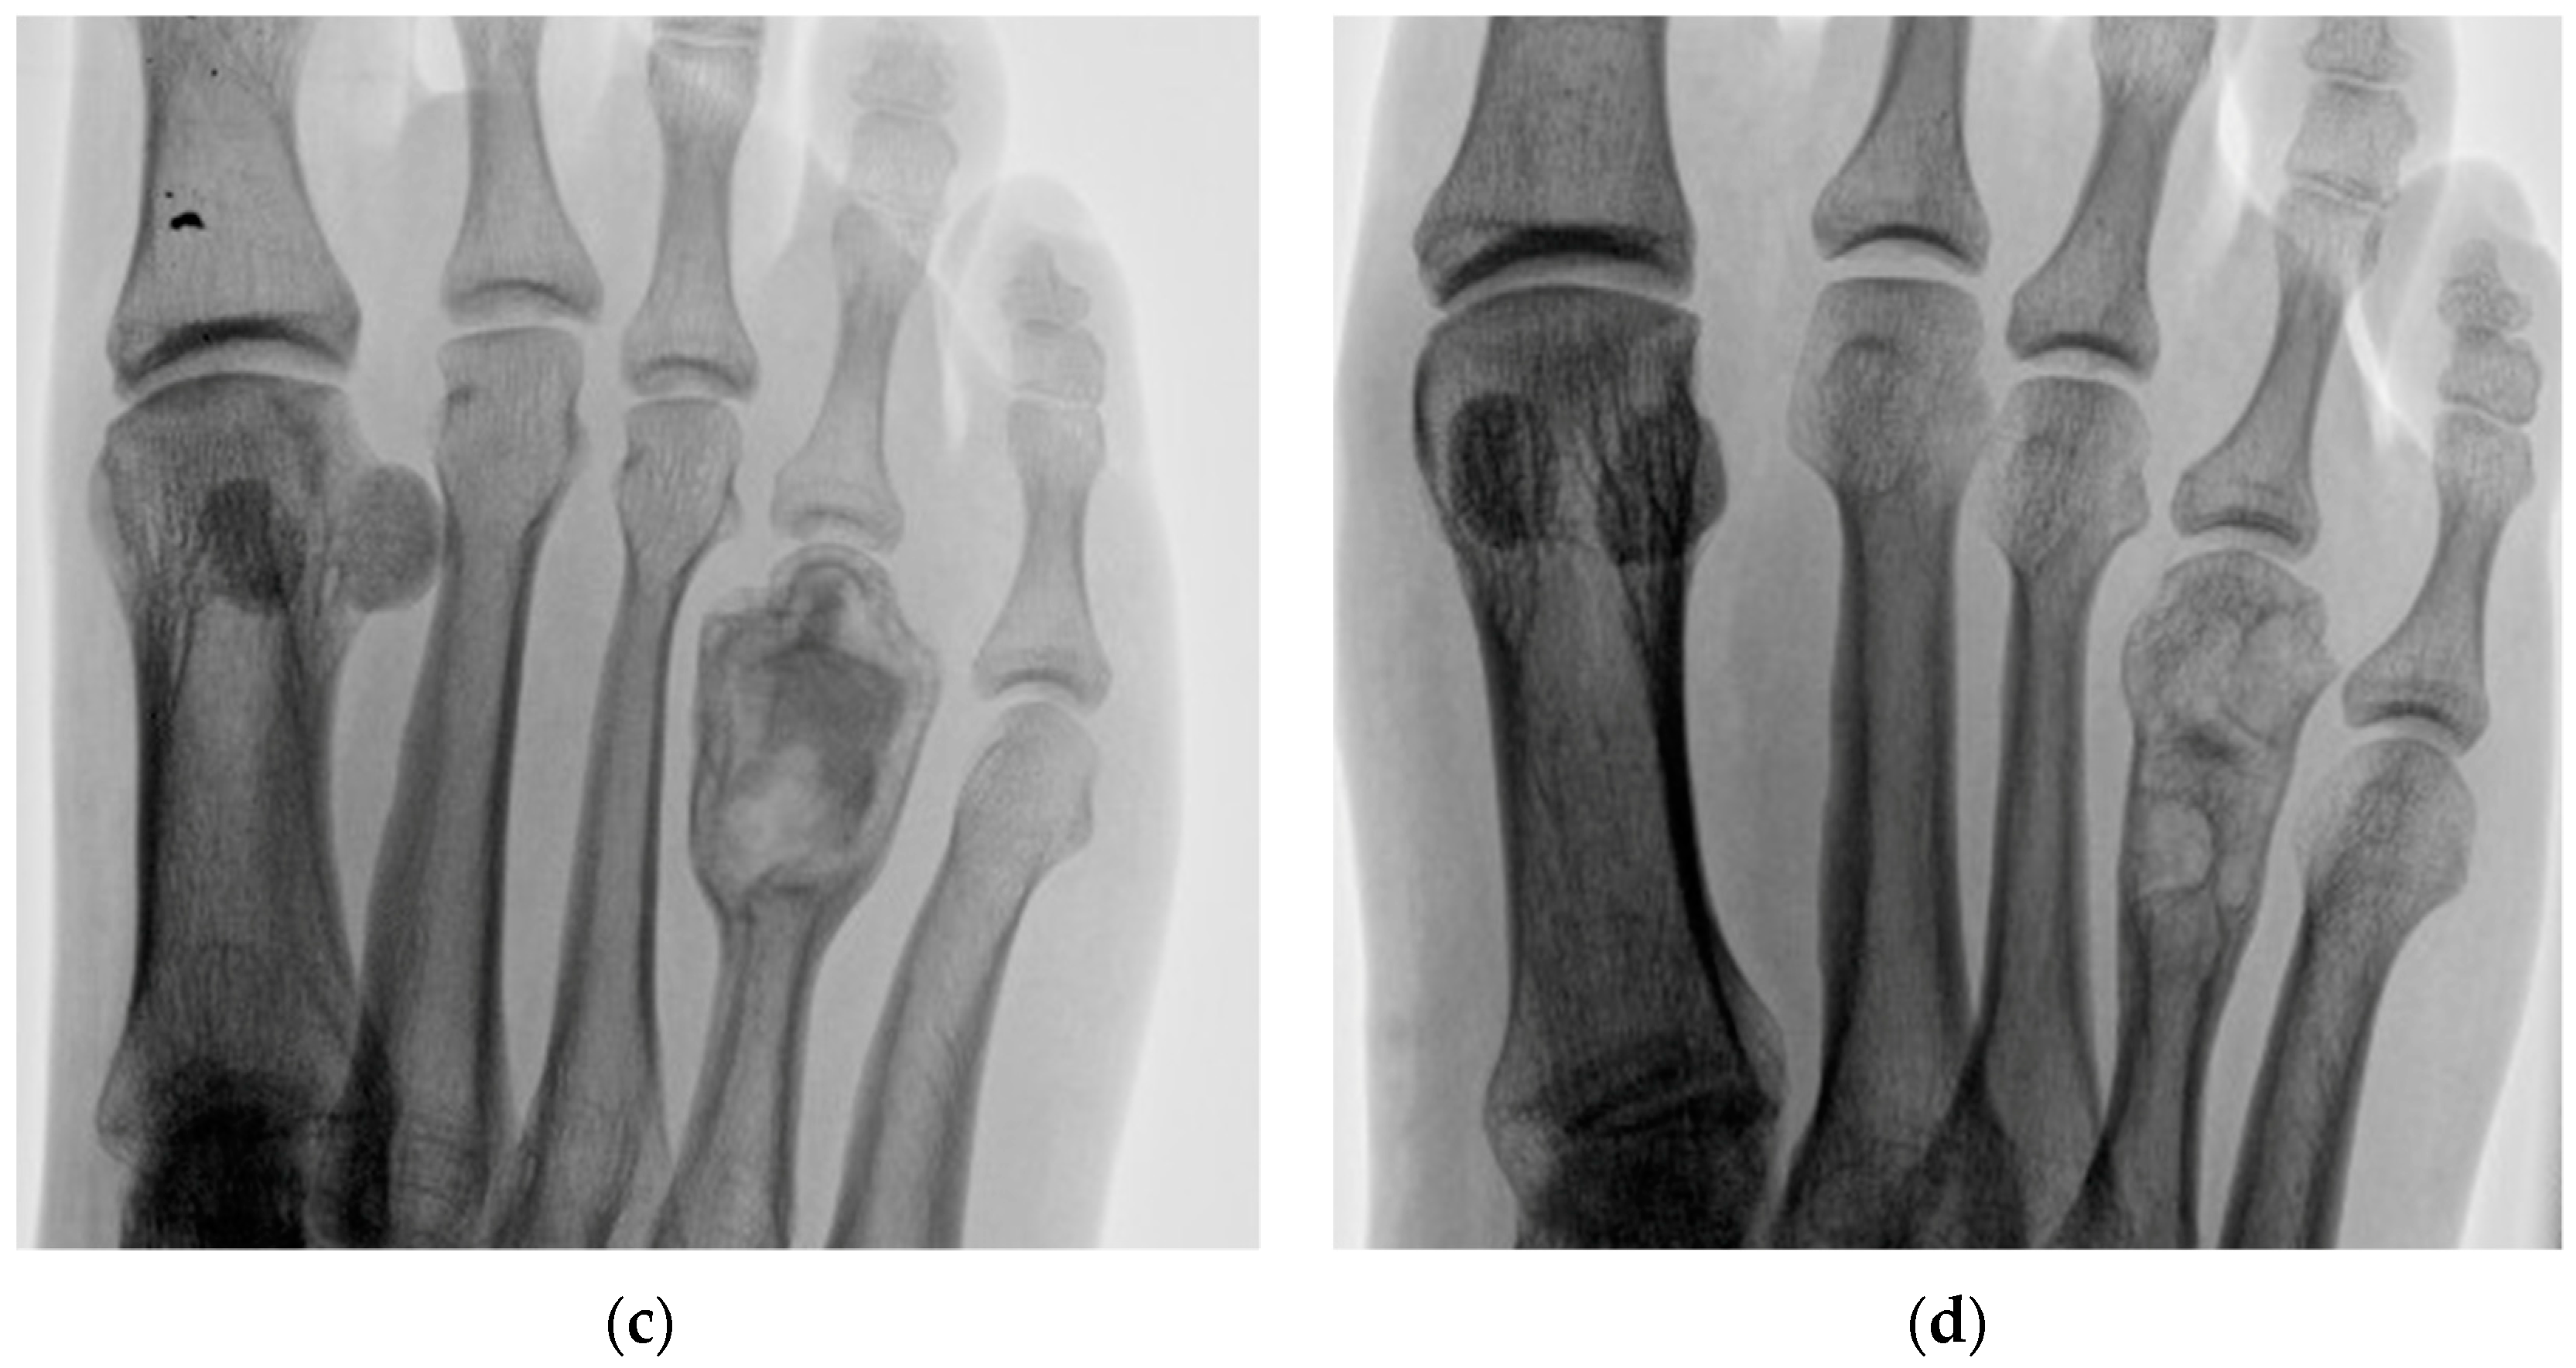

2 | 34 M | 1 | Left middle finger P1 | 32 | Enchondroma | 24 |

8 | 23 F | 1 | Left hand 2nd metacarpal | 27 | Aneurysmal bone cyst | 23 |